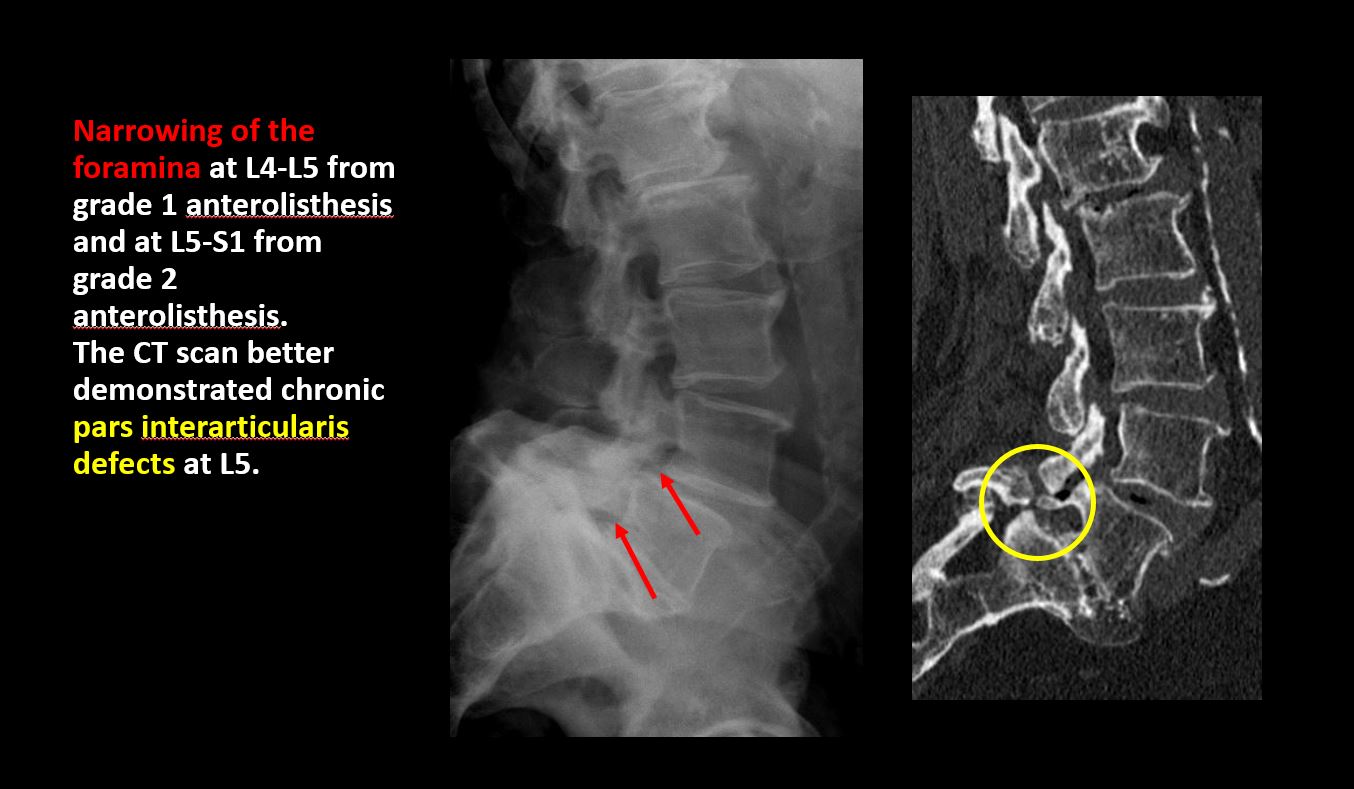

There is lucency or defect of the pars interarticularis from spondylolysis. |

There is anterior or posterior spondylolisthesis, subluxation, or rotational abnormality at a disc space. |

There is narrowing or encroachment of a neural foramen other than from degenerative change. |